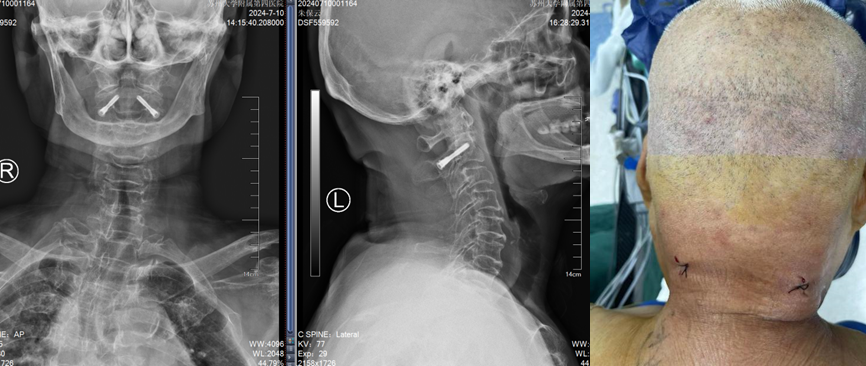

入院完善术前检查后,骨科姜为民主任团队在骨科机器人的辅助下,精准而迅速地置入了两枚由团队设计的枢椎椎弓根专用拉力螺钉,仅留下两个不足1cm的切口。手术过程顺利,手术时间仅38分钟。患者术后第一天就可以佩戴颈托下床行走,第二天即可出院回家休养。

术后复查提示骨折复位,置钉精准